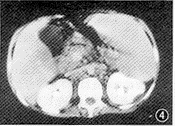

例2 男,19岁。因反复高热、全身浅表淋巴结肿大、气短、乏力、腹胀10个月入院。患者自发病以来,曾多次B超检查,发现有腹水,量多时不能平卧。本次入院时体检:体温39.5℃,体质消瘦,中度贫血貌,全身浅表淋巴结肿大,直径达0.5~1.0cm。右下肺叩诊呈浊音,听诊呼吸音稍弱。肝肿大,肋下3cm 处扪及;脾肿大,肋下5cm 处扪及,于左下肢及腰部可见多个结节,直径约0.2~0.5cm,触痛明显。阴囊明显肿大。不同时间的胸片示右侧少量胸腔积液,右上肺结节影,肺纹理增多紊乱,右上纵隔及肺门肿块等(图1)。脊柱片示第1腰椎椎体呈前凹后凸,椎间隙不等宽,发育异常(图2)。胸骨摄片示胸骨第3、4节未融合,骨龄延迟。胸部CT示右上纵隔及右肺门团块影,脂肪密度,其CT值为-32~-2HU,内部可见分隔,上腔静脉受压向前移位;增强扫描肿块无明显强化(图3)。腹部CT示肝脾肿大,尤以脾脏增大为甚,肠系膜及腹腔淋巴结受累,形成大小不等的结节影,部分融合成团块状。肾实质及肾周筋膜呈不规则低密度(图4)。左下肢皮下结节活检,病理报告为结节性脂膜炎。

图4 腹部CT增强扫描,可见肝脾肿大,尤以脾脏增大为甚。肠系膜及腹腔淋巴结受累,形成大小不等的结节影,部分融合成团块状。肾及肾周脂肪受累,表现为肾实质及肾周筋膜不规则低密度